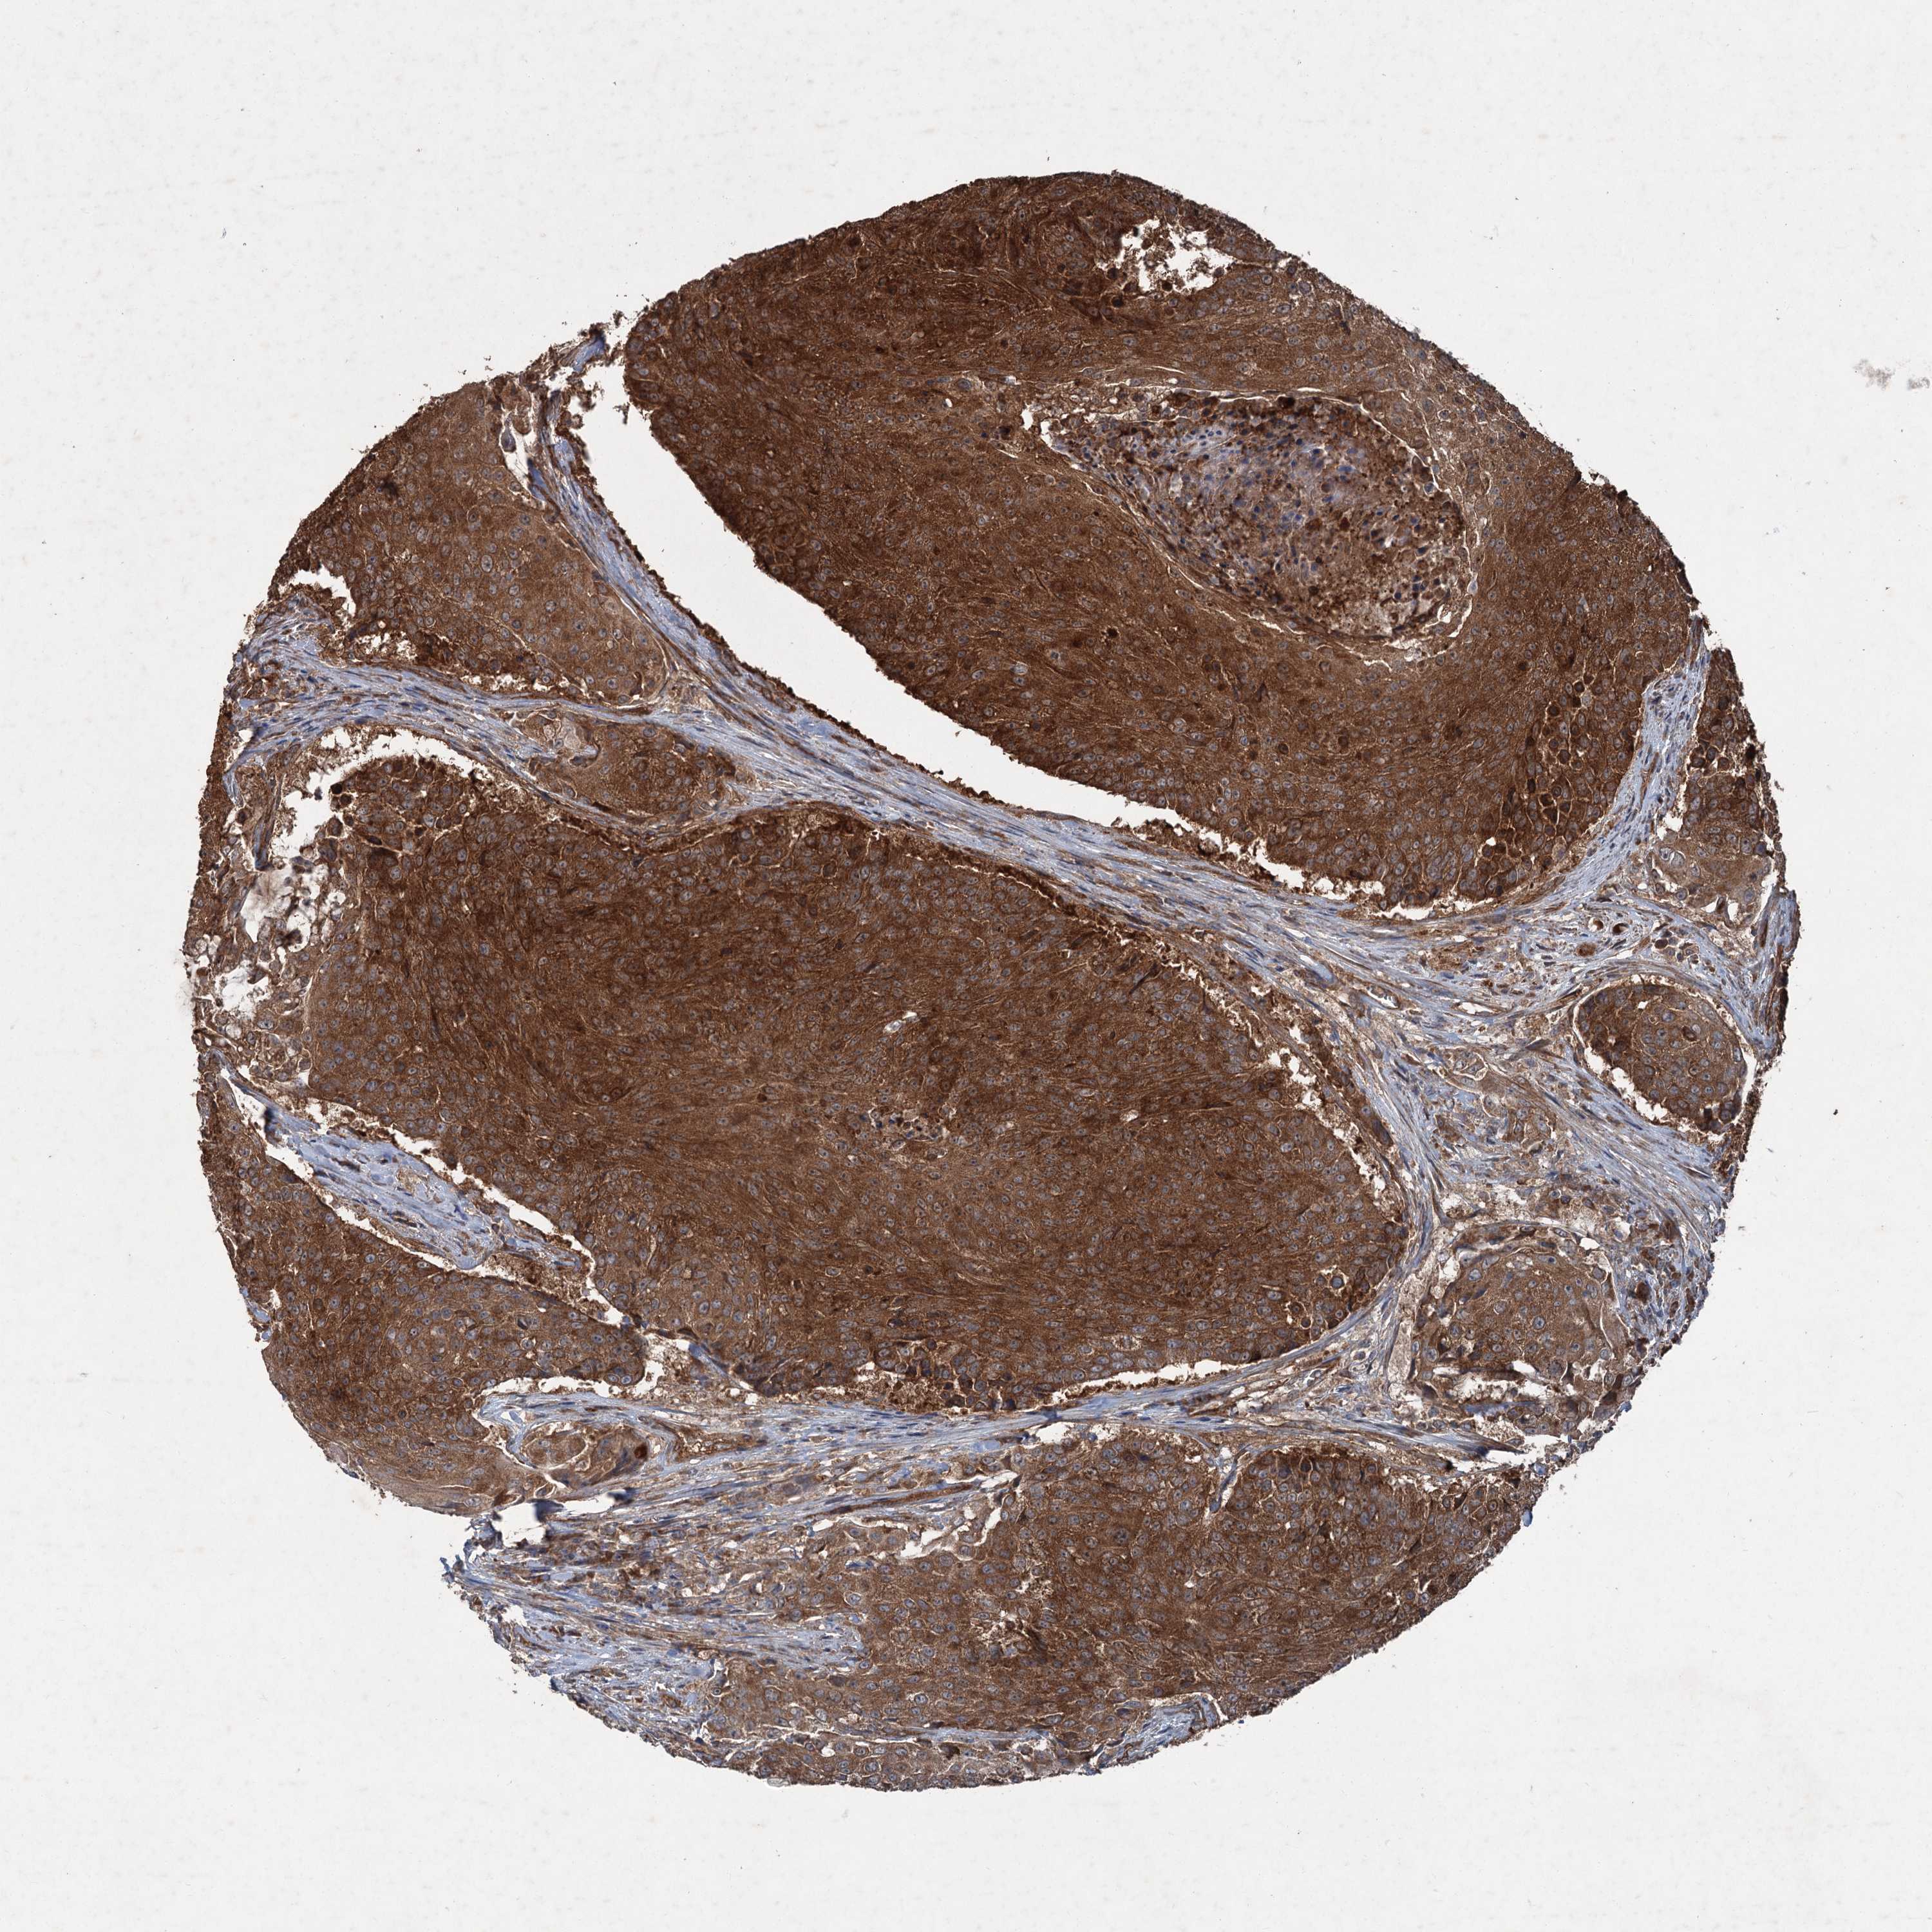

UROTHELIAL CANCER - Protein expressioni

A mouse-over function shows sample information and annotation data. Click on an image to view it in a full screen mode. Samples can be filtered based on level of antibody staining by selecting one or several of the following categories: high, medium, low and not detected. The assay and annotation is described here.

Note that samples used for immunohistochemistry by the Human Protein Atlas do not correspond to samples in the TCGA dataset.

Antibody stainingi

Antibody staining in the annotated cell types in the current human tissue is reported as not detected, low, medium, or high, based on conventional immunohistochemistry profiling in selected tissues. This score is based on the combination of the staining intensity and fraction of stained cells.

Each image is clickable and will lead to virtual microscopy that enables deeper exploration of all samples and also displays staining intensity scores, fraction scores and subcellular localization as well as patient and tissue information for each sample.

Antibody HPA039332

Staining

High

Medium

Low

Not detected

Intensity

Strong

Moderate

Weak

Negative

Quantity

>75%

75%-25%

<25%

None

Location

Urothelial carcinoma, High grade

Urothelial carcinoma, Low grade

Urothelial carcinoma, NOS